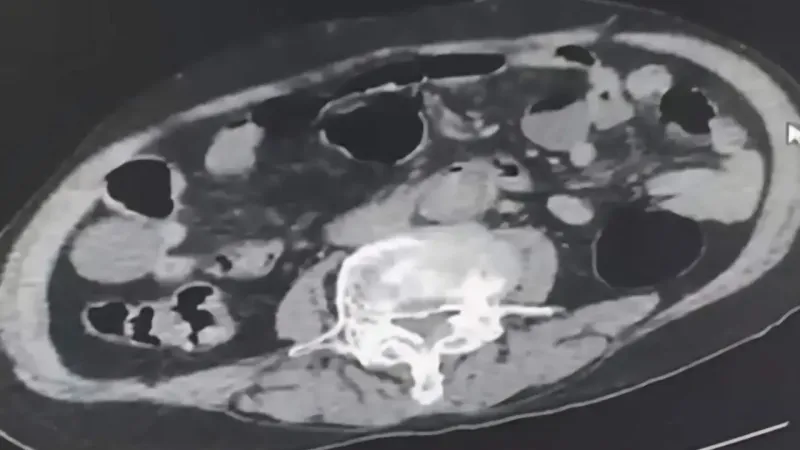

Şüpheliler üzerinde ve adreslerinde yapılan aramalarda, 6 parça halinde toplam 145 gram metamfetamin ile 260 gram sıvı halde sentetik ecza maddesi ele geçirildi. Yapılan incelemede yabancı uyruklu şüphelilerden birinin uyuşturucu maddeyi cinsel organında sakladığı ortaya çıktı.